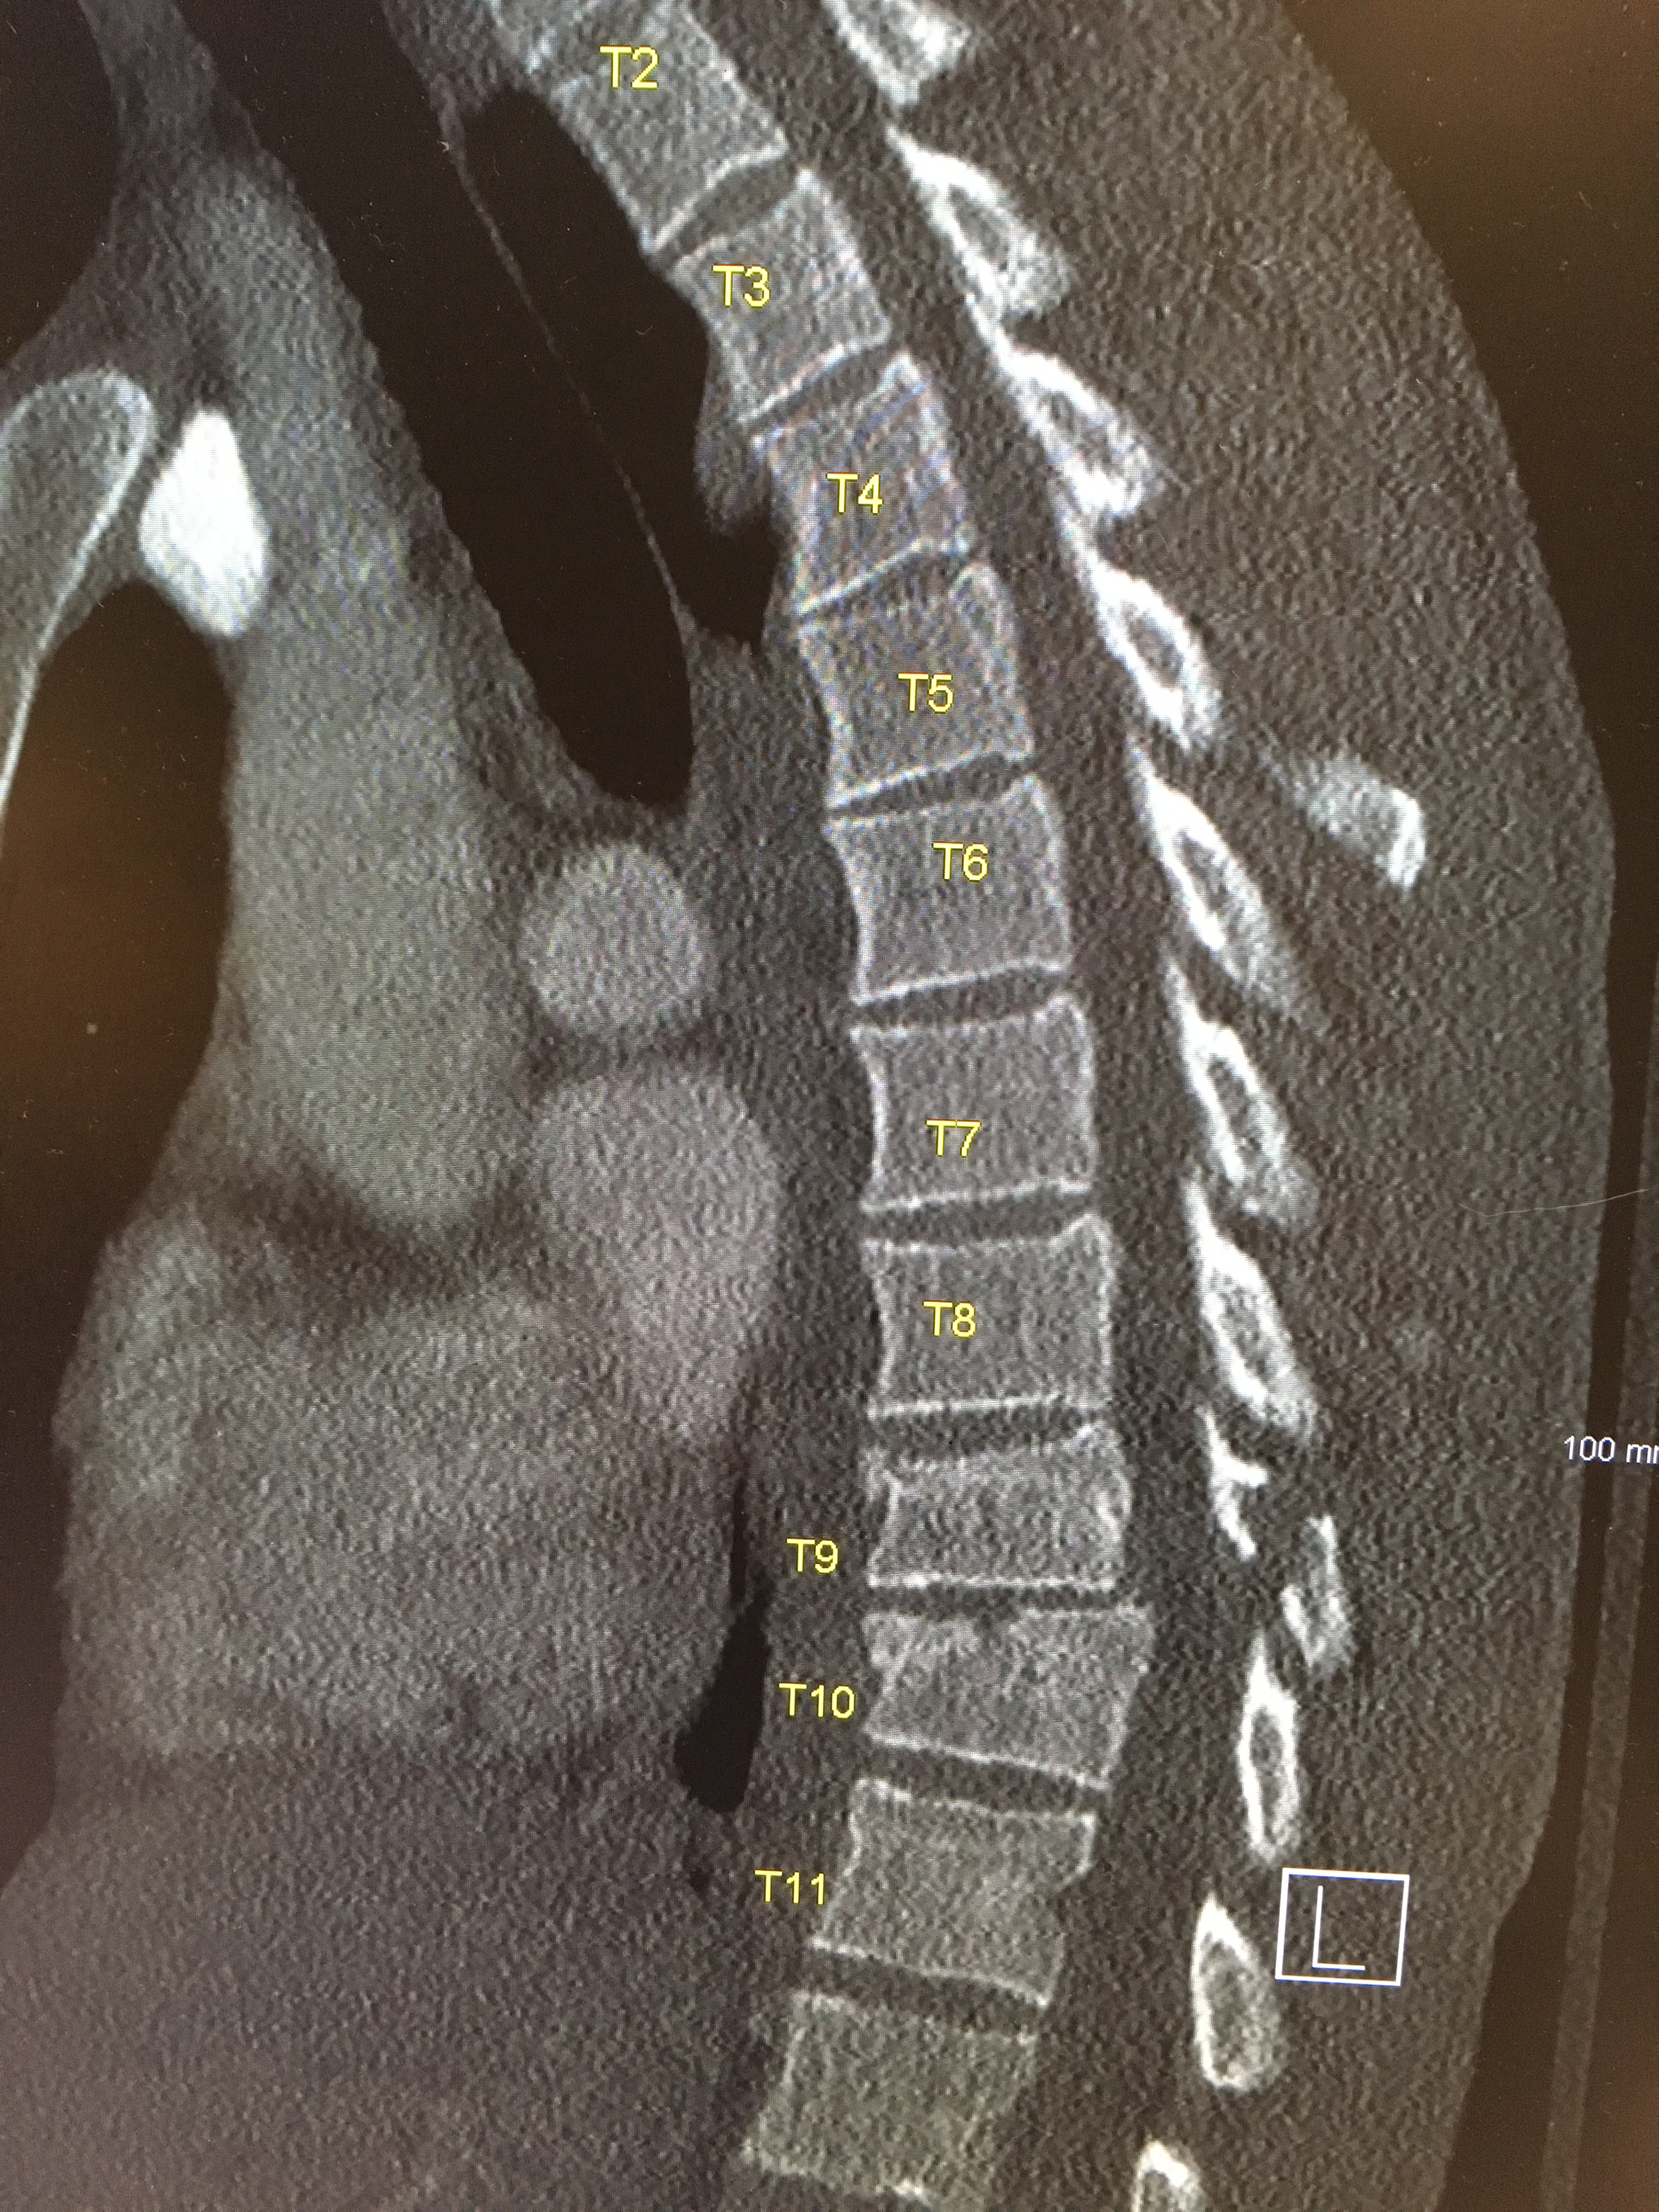

Adam: I broke my T8 to T11. That’s fine so they put pins in there, I broke my iliac crest, so the top of my hipbone sheared right off and then as they said that I had open lacerations which are actually the biggest concern to them because of infection. There’s rock fall in there, but it was down to the bone across all my hip. Which is pretty horrible and the other parts of me were sore but they weren’t as critical.